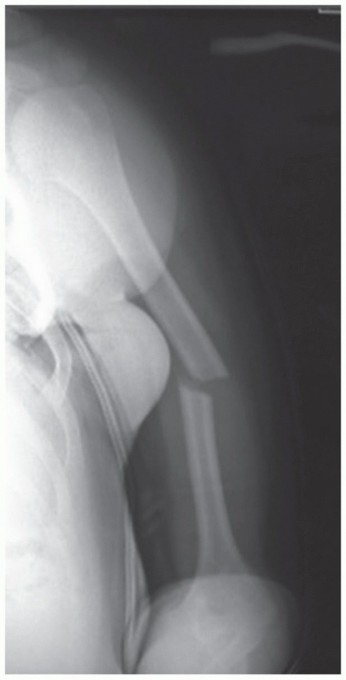

DEFINITION Brett D. Owens Joanna G. Branstetter Thomas P. Goss Intra-articular scapular fractures include fra…